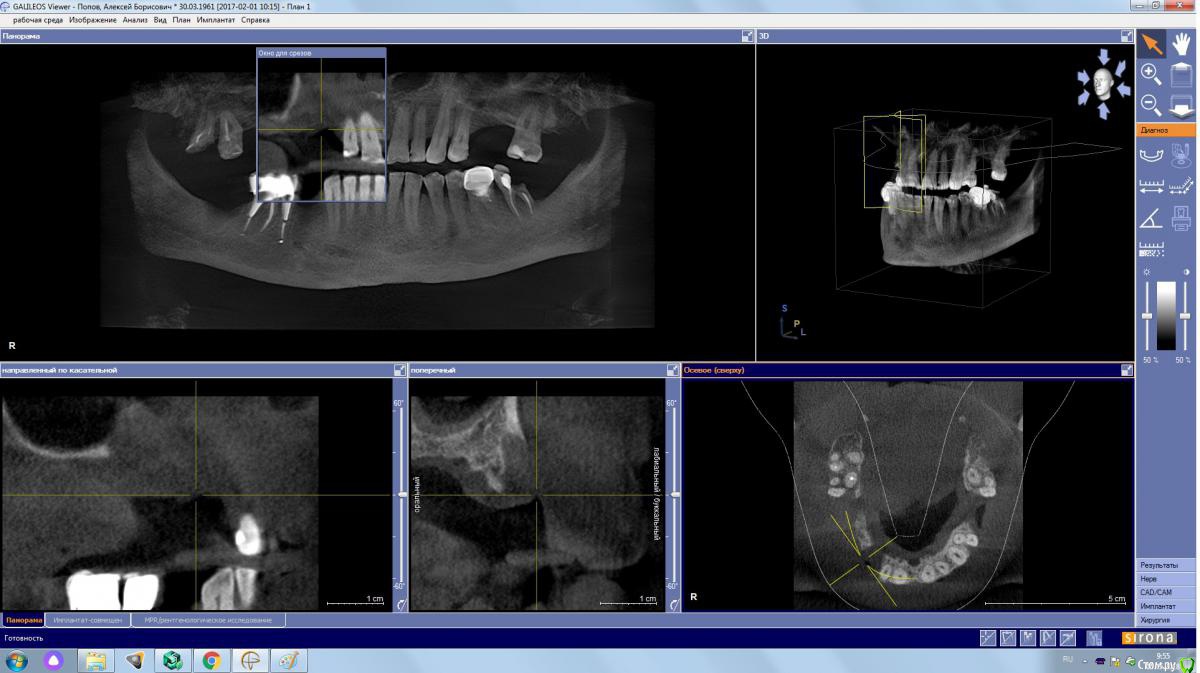

kamranchick Опубликовано 4 мая, 2018 Поделиться Опубликовано 4 мая, 2018 Обратился пациент после очередной халтуры которыми радуют меня коллеги из соседних клиник)фотопротокол ни как у Сашки Гудкова но более-менее понятно))Обратился пациент, в соседней клинике удаляли зуб, корень протолкнули в пазуху, далее пациент попал в ЧЛХ, там сделали радикальную гайморотомию, все достали, и вот попал пациент ко мне, так как в другой клинике сказали что у вас тут залу*а, а не кость, ну и погнали.1. пытался остро отслоиться, перфа на перфе, закрывал prf, мембранами, губками, стики бон + синус имплантация. ожидание 9 месяцев2. Пластика мягких тканей ожидание 2 месяца. 13 Ссылка на комментарий

kamranchick Опубликовано 4 мая, 2018 Автор Поделиться Опубликовано 4 мая, 2018 а рентген?))Есть кт до, и есть панорамник)завтра могу это все скинуть если интересно Ссылка на комментарий

Eddie Опубликовано 7 мая, 2018 Поделиться Опубликовано 7 мая, 2018 У вас тут в области 13 и 15 диаметры имплантатов 3.5(3.8)? Выдержат такую конструкцию? Ссылка на комментарий

kamranchick Опубликовано 7 мая, 2018 Автор Поделиться Опубликовано 7 мая, 2018 У вас тут в области 13 и 15 диаметры имплантатов 3.5(3.8)? Выдержат такую конструкцию?ну да, а что ей будет) связанная конструкция, на израиле 3.75, служат) Ссылка на комментарий